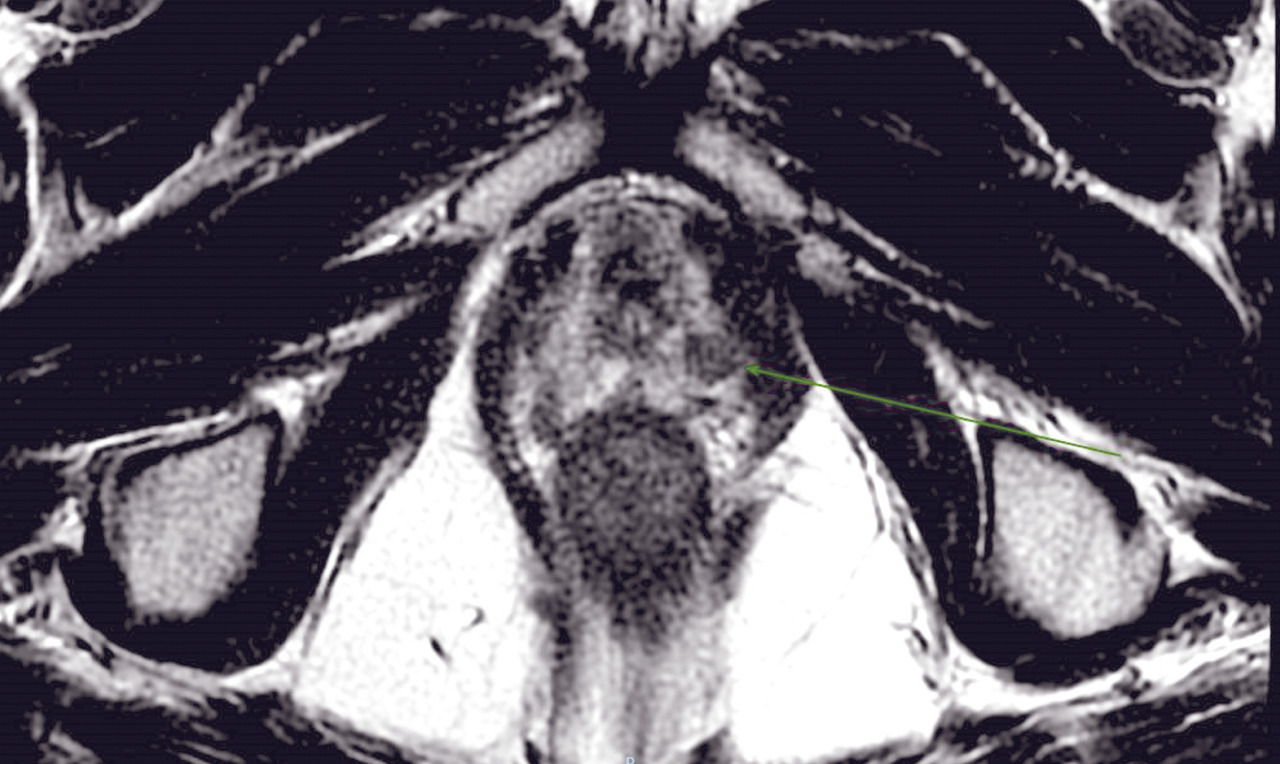

IRM de la prostate

À ce jour, avec la diffusion d’outils de plus en plus sophistiqués et précis pour effectuer des biopsies avec fusion d’images entre l’IRM multiparamétrique et l’échographie transrectale en temps réel, la biopsie avec connaissance de l’anatomie prostatique sur la base des images d’IRM réalisée sous guidage échographique est devenue une approche indispensable, permettant de faire évoluer les biopsies systématisées, réalisées « à l’aveugle», vers des biopsies ciblées. De nombreuses études ont montré que l’échantillonnage ciblé, en plus de l’approche systématique, est mieux corrélé au score de Gleason pathologique, tandis que d’autres ont montré une meilleure performance en termes de sensibilité et de spécificité de la biopsie ciblée par rapport à la réalisation des biopsies avec approche systématique, réduisant de manière significative le taux de détection des tumeurs cliniquement non significatives. Par conséquent, la réalisation de l’IRM avant de programmer les biopsies est de plus en plus recommandée afin de :

Dans ce scénario, des limites importantes peuvent découler de l’expérience différente des radiologues dans l’interprétation du protocole multiparamétrique : en effet, la variabilité inter-observationnelle et l’hétérogénéité dans la définition de l’examen en tant que positif ou négatif restent cruciales.

Contrairement à la tomodensitométrie (TDM), la résolution spatiale de l’image garantie par l’IRM permet d’élucider l’anatomie zonale de la glande prostatique et de distinguer la portion périphérique de la glande et le tissu néoplasique, qui a un signal intrinsèque différent. De plus, pour les mêmes raisons, l’IRM est en mesure de mieux représenter toutes les structures pelviennes restantes, avec une clarification remarquable de leurs rapports (vessie, rectum, muscles, structures squelettiques, vaisseaux). Ces caractéristiques rendent désormais l’utilisation de l’IRM multiparamétrique également essentielle à des fins de planification thérapeutique (bilan d’extension locorégional avant traitement local, par exemple de chirurgie ou de radiothérapie externe).